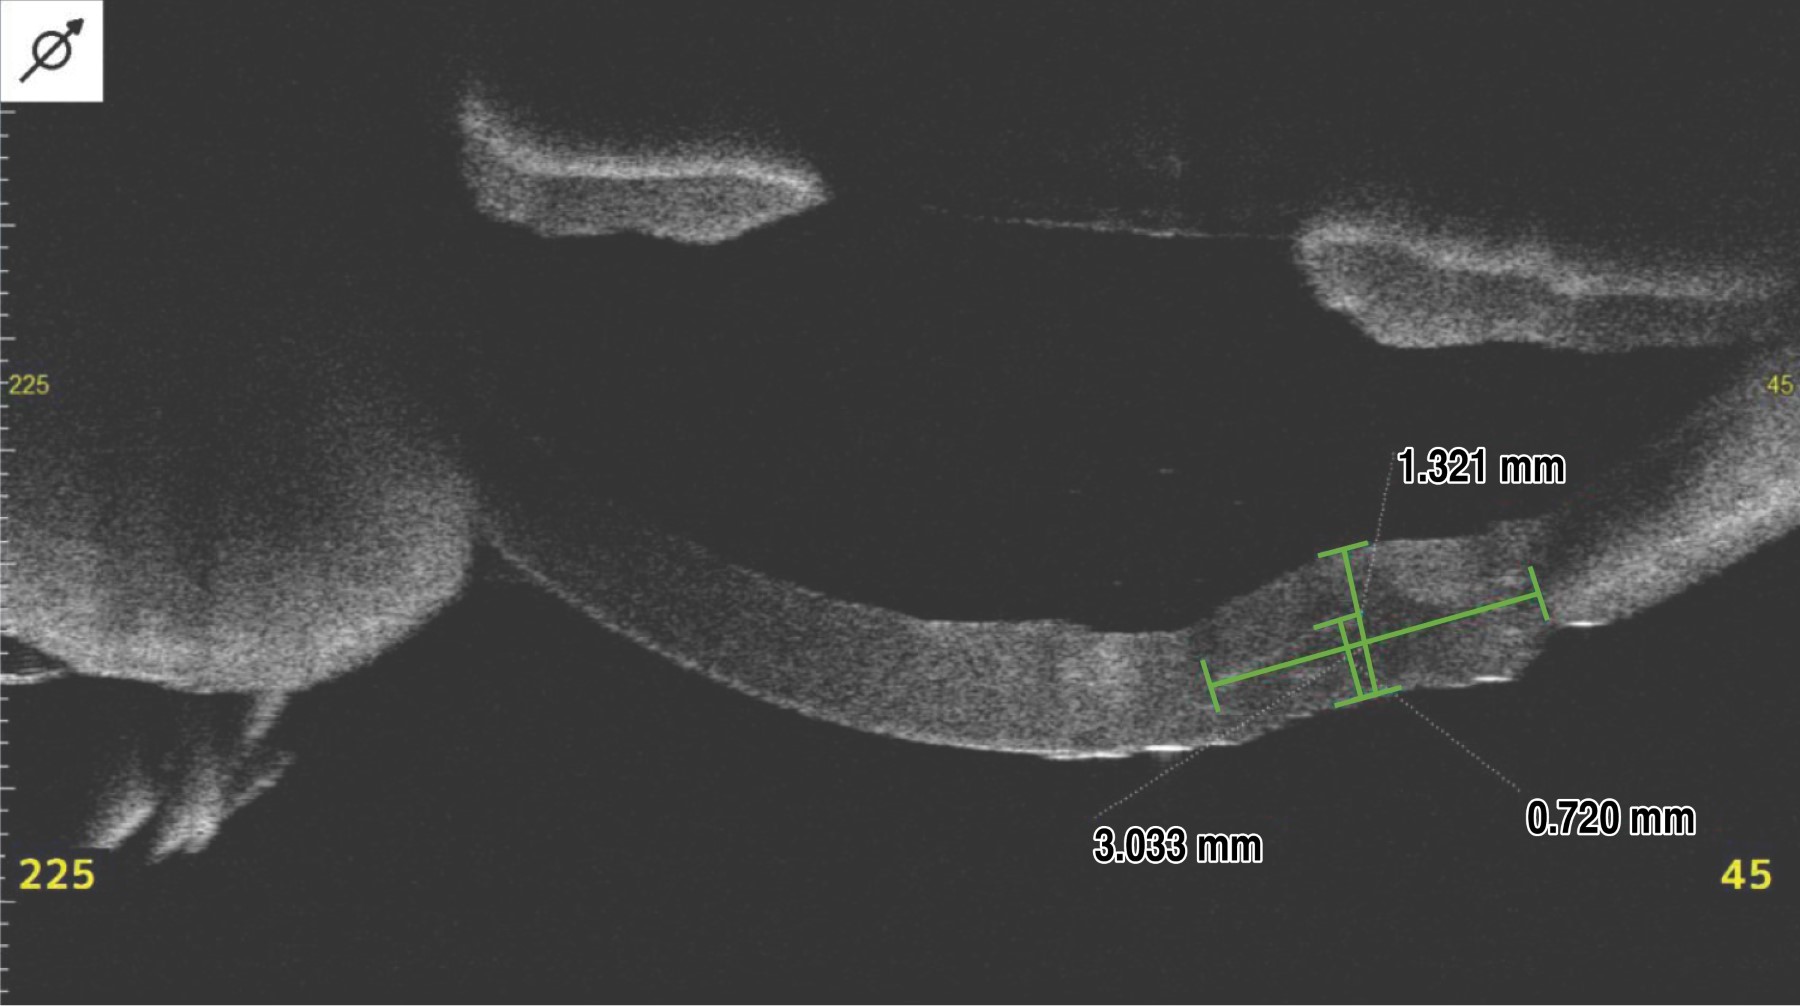

Se realizó tomografía de coherencia óptica de córnea (OCT, por sus siglas en inglés) del segmento anterior donde se identificó cuerpo extraño corneal en estroma profundo, con un grosor corneal total de 1.11 mm y de área afectada una profundidad de 0.727 mm con necrosis activa de 2.6 mm de diámetro (Figura 2).

El postquirúrgico inmediato a las 24 horas, el paciente se refirió estable con disminución significativa del proceso inflamatorio palpebral y síntomas oculares (Figura 3C). En el estudio OCT, a la semana del injerto de tejido corneal, se observó el injerto de 720 micras, limitado a la zona de necrosis secundaria resecada (Figura 5). Con adecuado registro oftalmológico en sus evaluaciones de control (Tabla 1).